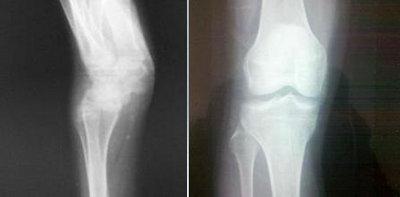

(图:王先生的腿严重变形,膝关节明显微肿)

(图:从X光片上可明显看出王先生的膝关节已恢复正常)